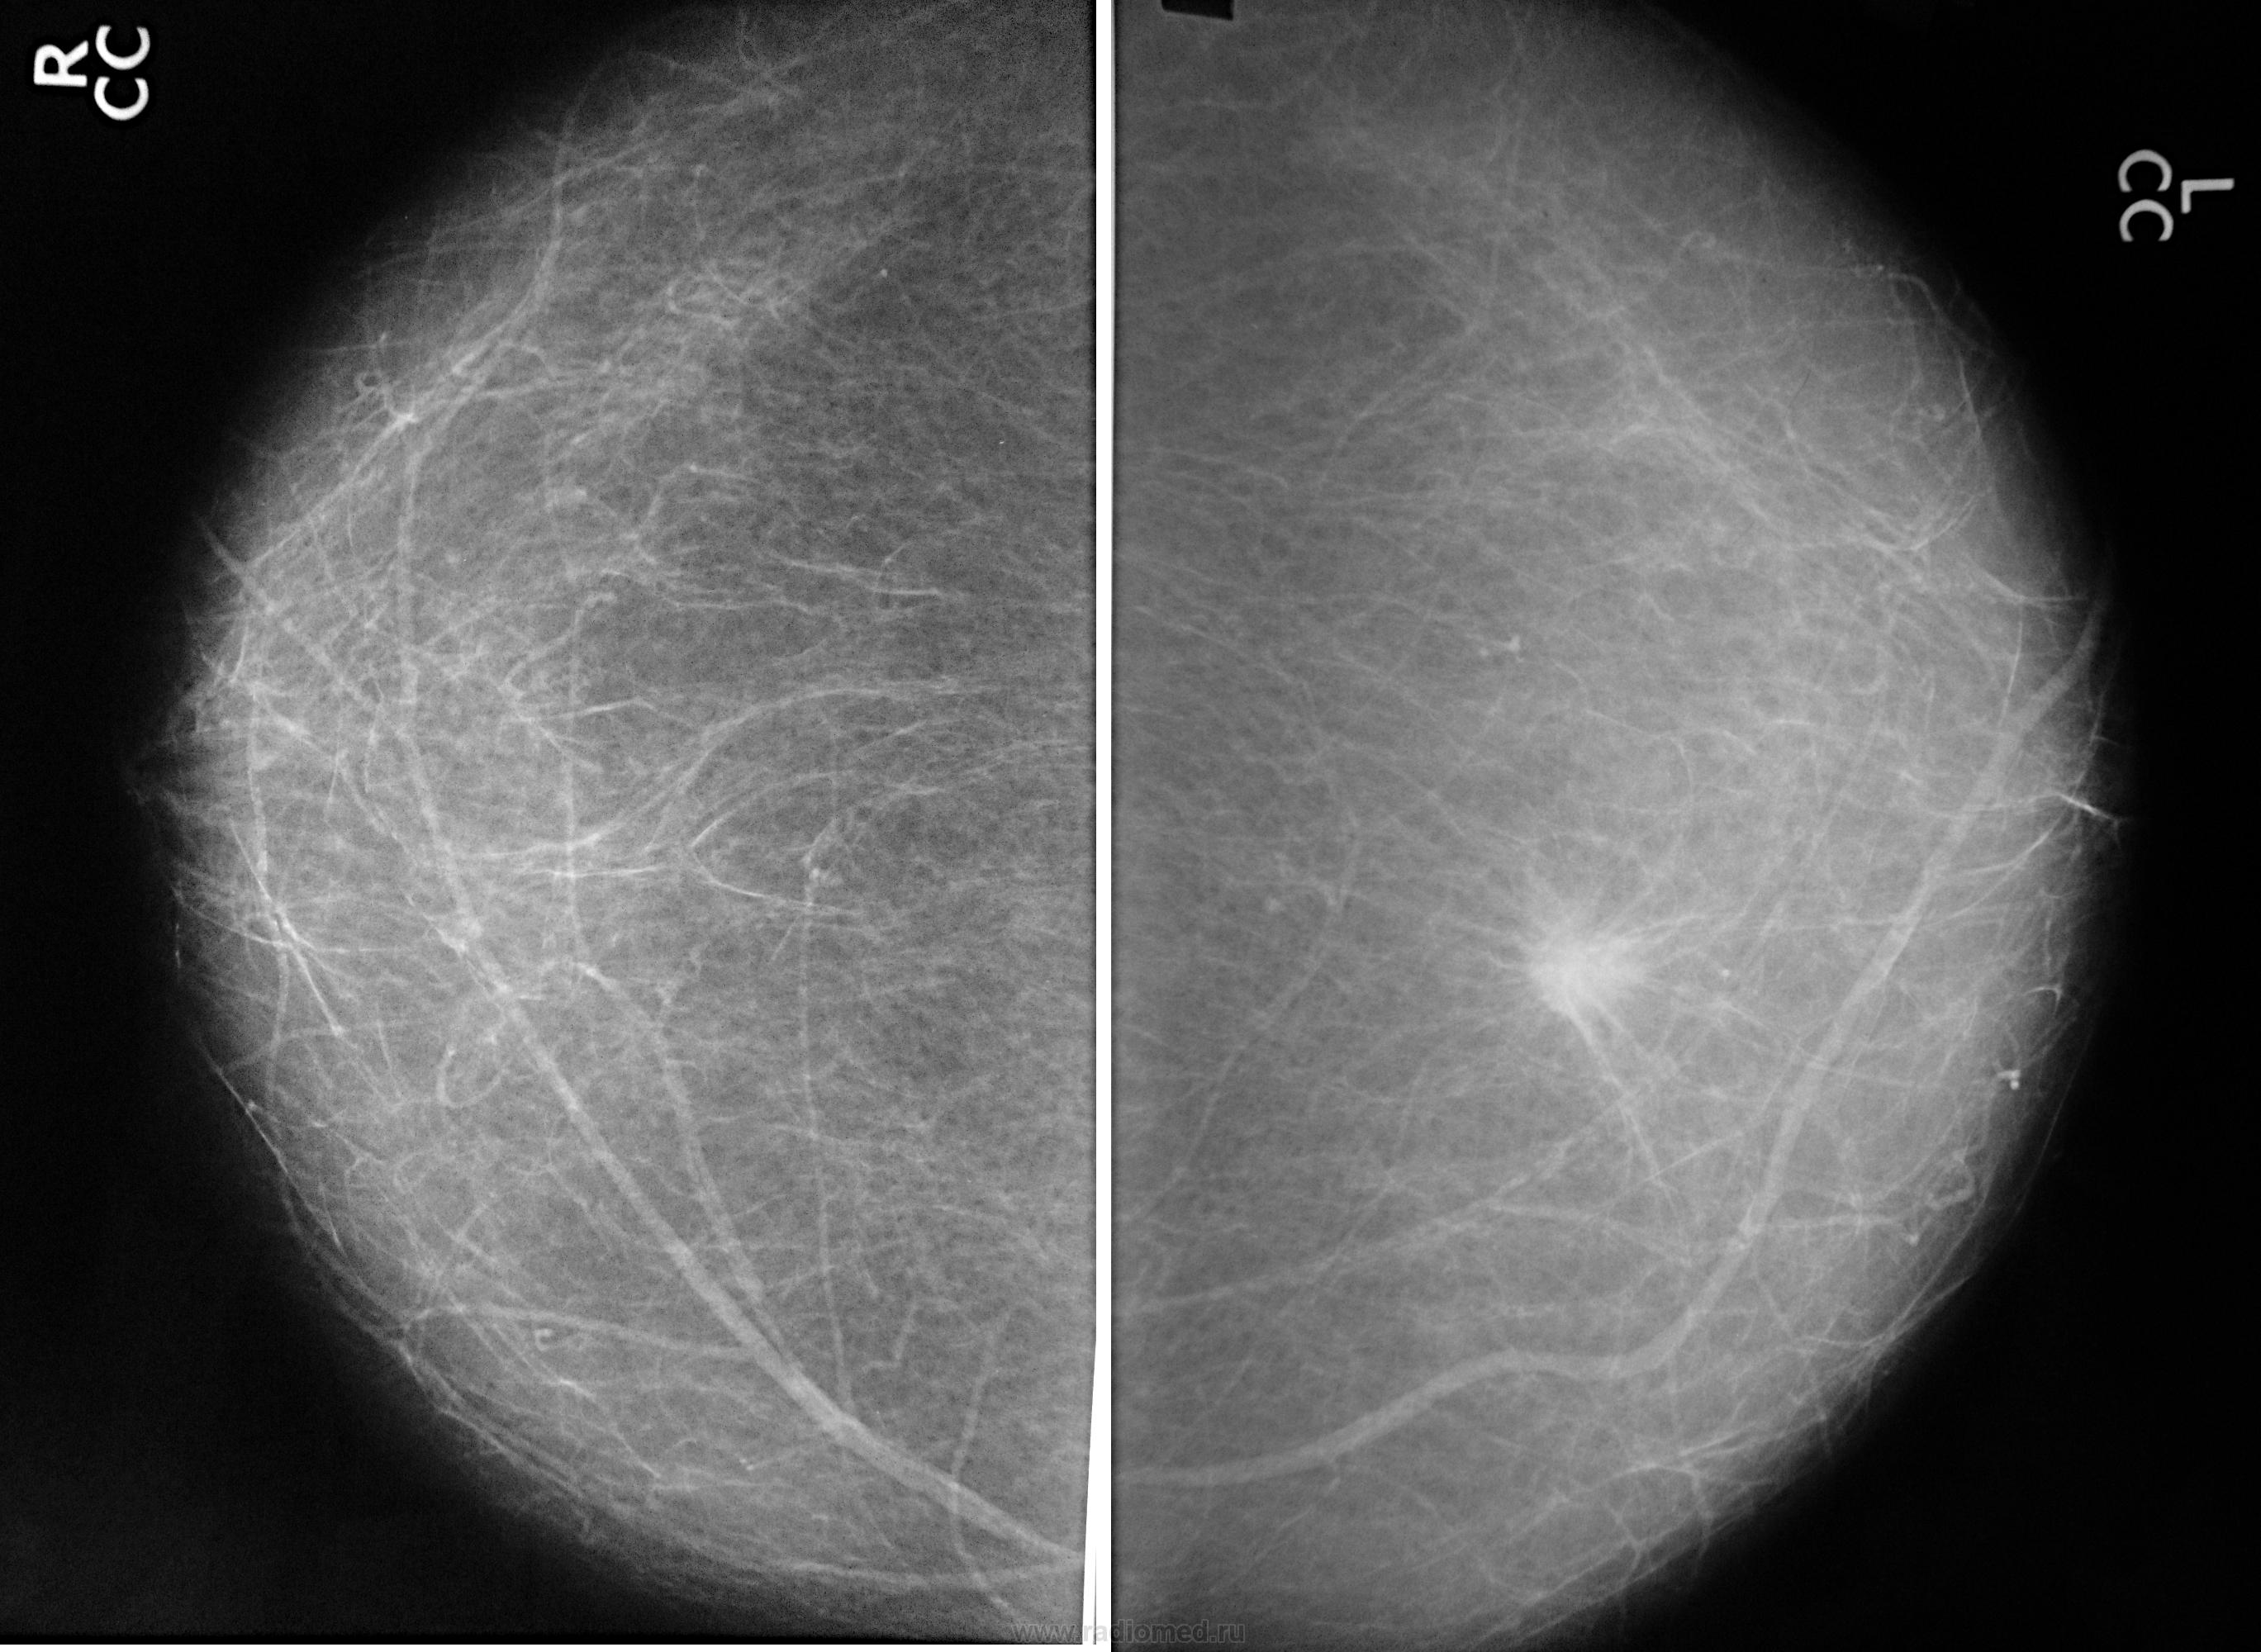

Фиброаденома молочной железы - доброкачественное образование, которое часто встречается у женщин. Оно может быть обнаружено при помощи различных методов диагностики, включая маммографию. Ниже представлены фотографии, помогающие понять, как выглядит данное заболевание.

Маммография и ее роль в диагностике фиброаденомы молочной железы

Маммография - это рентгенологическое исследование молочных желез. Оно позволяет выявить различные изменения в тканях, включая фиброаденому. На маммограммах можно увидеть структурные особенности опухоли и отследить ее динамику во времени.